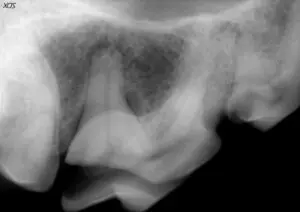

Detailed examination and dental radiography (x-rays) are required when assessing and deciding the proper treatment for fractured teeth like the one seen below.